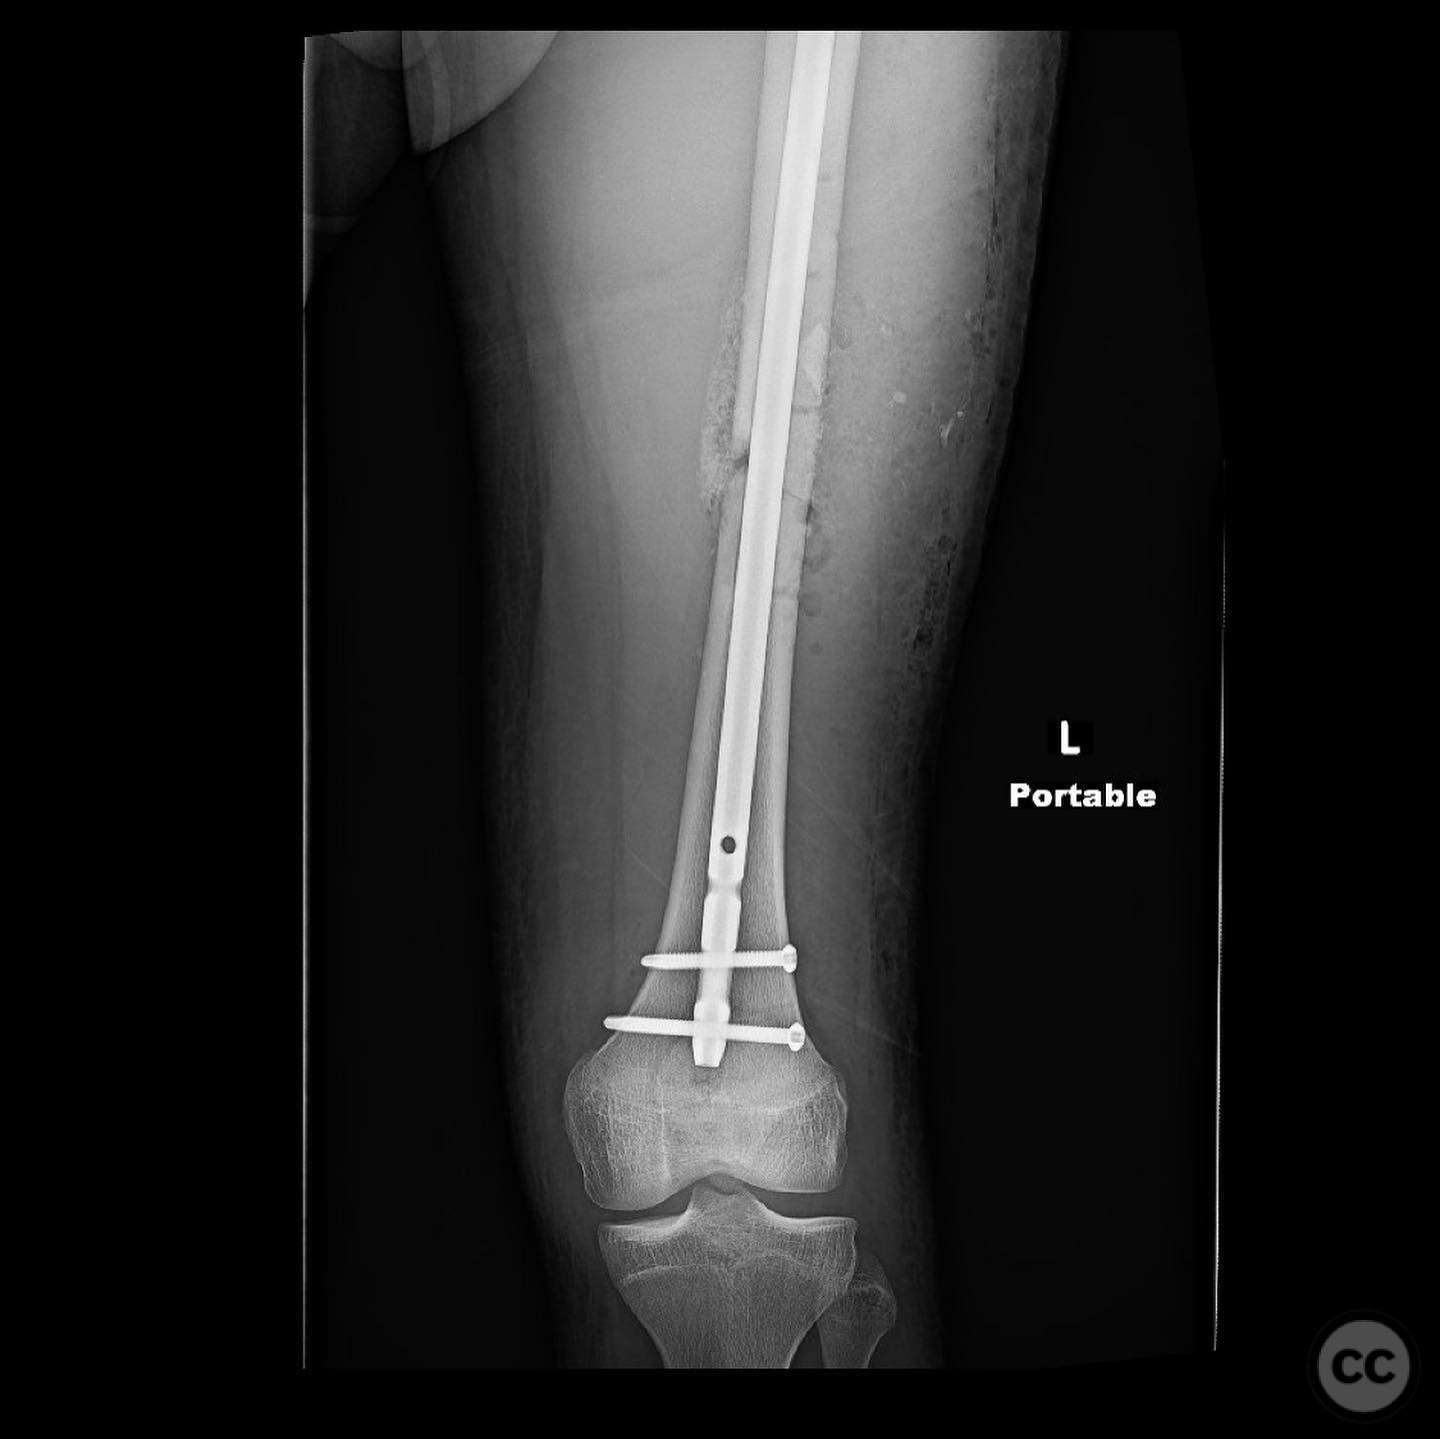

Postoperative protocol:   Postoperative rehabilitation included early mobilization with toe-touch weight-bearing (TTWB) for 6 weeks, followed by progressive weight-bearing as tolerated. Range of motion exercises were initiated early to prevent joint stiffness.

Orthopaedic implants used:   Intramedullary nail, autologous bone graft from reamings.